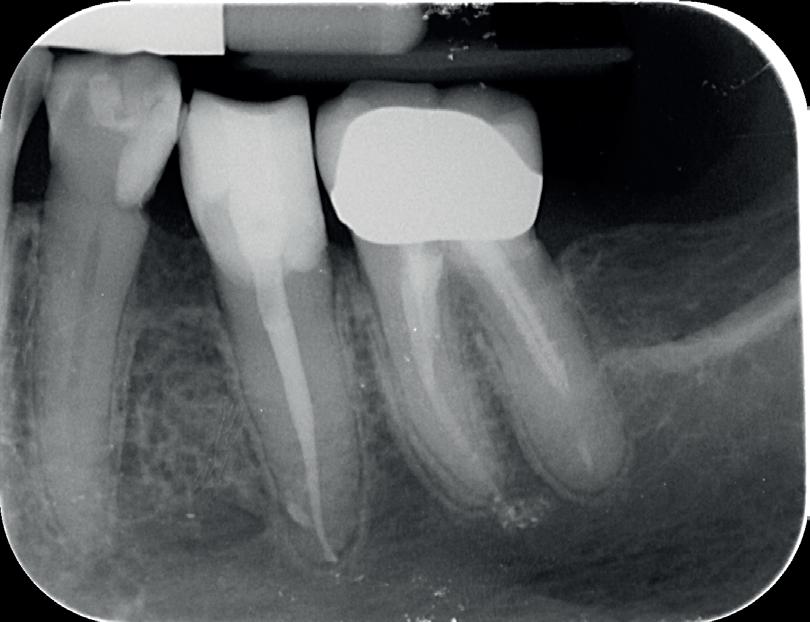

3. De wortel van element 11 is voor een groot deel vervangen door bot. Er is geen duidelijk PDL meer zichtbaar aan de distale zijde.

De snelheid waarmee deze resorptie gaat, is lastig te voorspellen. Wel weten we dat het de dezelfde snelheid kan aannemen als de remodeling van het bot. Dit kan erg snel zijn voor de pubertijd (foto 3).5 Er is helaas niets wat we kunnen doen om deze vorm van resorptie te beïnvloeden. De beschadiging van het PDL kunnen we niet meer terugdraaien. Het enige dat we kunnen doen is het verwijderen van de necrotisch geïnfecteerde pulpa. Dit zal infectie gerelateerde resorptie in ieder geval voorkomen. Deze vorm van resorptie kan ook erg hard gaan (foto 4).

Het element is in fysiologisch zout bewaard, maar de kans dat de PDL-cellen het overleefd hebben, is zeer klein. De kans dat er ankylose gerelateerde resorptie zal optreden na 31 uur extra alveolair is dus heel erg

groot. Aangezien we te maken hebben met een dame van 18 jaar met een avulsie van een centrale incisief, is implantologie op dit moment niet ideaal.6 Graag zouden we dus tijd winnen, om een meer geschikte leeftijd voor implantologie te bereiken. Om de tijd te overbruggen, willen we zo veel mogelijk bot behouden. Een ‘lege’ alveole heeft dan niet de voorkeur.

In deze situatie is er een aantal behandelmogelijkheden; decoronatie, autotransplantatie of het element terugplaatsen. De voorkeur gaat uit om het element te behouden en dus terug te plaatsen.

In dit geval heb ik mijn collega die belde voor advies, geadviseerd om contact op te nemen met de implantoloog waar ze mee samenwerkt. De kans dat implantologie op termijn nodig zal zijn, is namelijk heel erg groot. De patiënt kon dezelfde dag nog terecht bij tandarts-implantoloog Tristan Staas. Naast de aanwezige solo is er een CBCT gemaakt (foto 5 en 6). De behandelmogelijkheden zijn hierna uitgebreid besproken.

Er is in deze casus door de implantoloog gekozen om element 21 terug te plaatsen, in de hoop dat het zo lang mogelijk goed blijft gaan. Het stolsel is met een implantaatboor uit de alveole verwijderd en de alveole is iets verruimd. Eigenlijk dezelfde procedure als bij een autotransplantatie. Hierna is het element uitgebreid afgespoeld met fysiologisch zout, teruggeplaatst en aan de spalk bevestigd. Voorheen was,